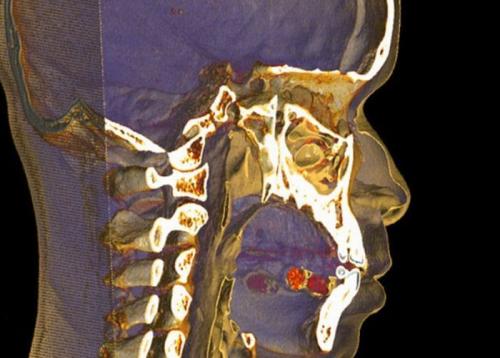

Кокаин под языком.